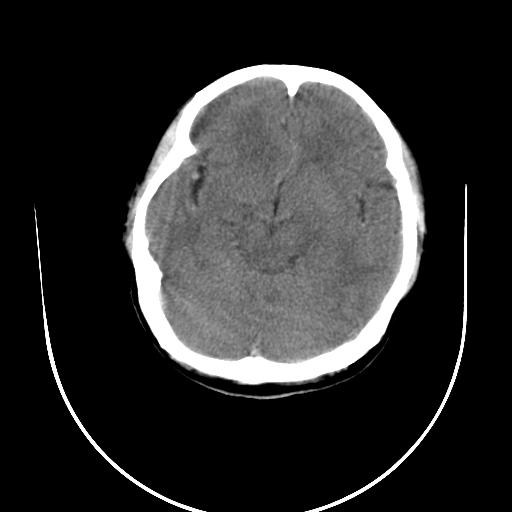

标题: CT10010:女/24岁,癫痫一周,发作时间不固定. [打印本页]

标题: CT10010:女/24岁,癫痫一周,发作时间不固定.

右侧额叶正常吗?

右额叶镰旁饱满.

右侧外侧沟?中央沟?可能有问题,不知以前有没有癫痫过,最好是增强下,排除局部血管畸形等病变

倒数第6幅图中线结构有点偏,而侧脑室额角未见异常,可结合增强扫描。